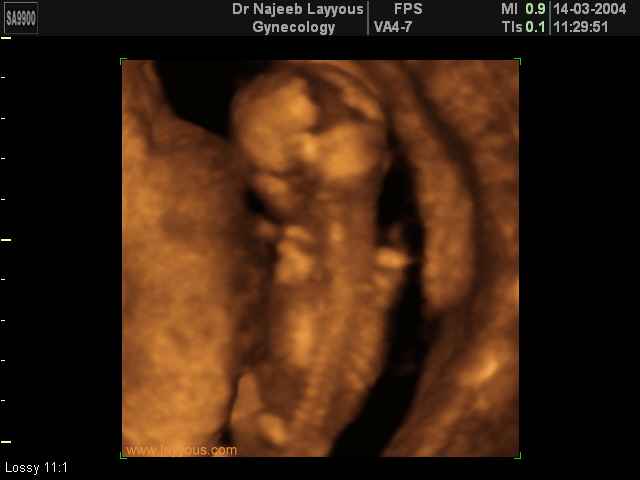

3D Photos échographie des parties du fœtus | Dr N Layyous

3D Photos échographie des parties du fœtus